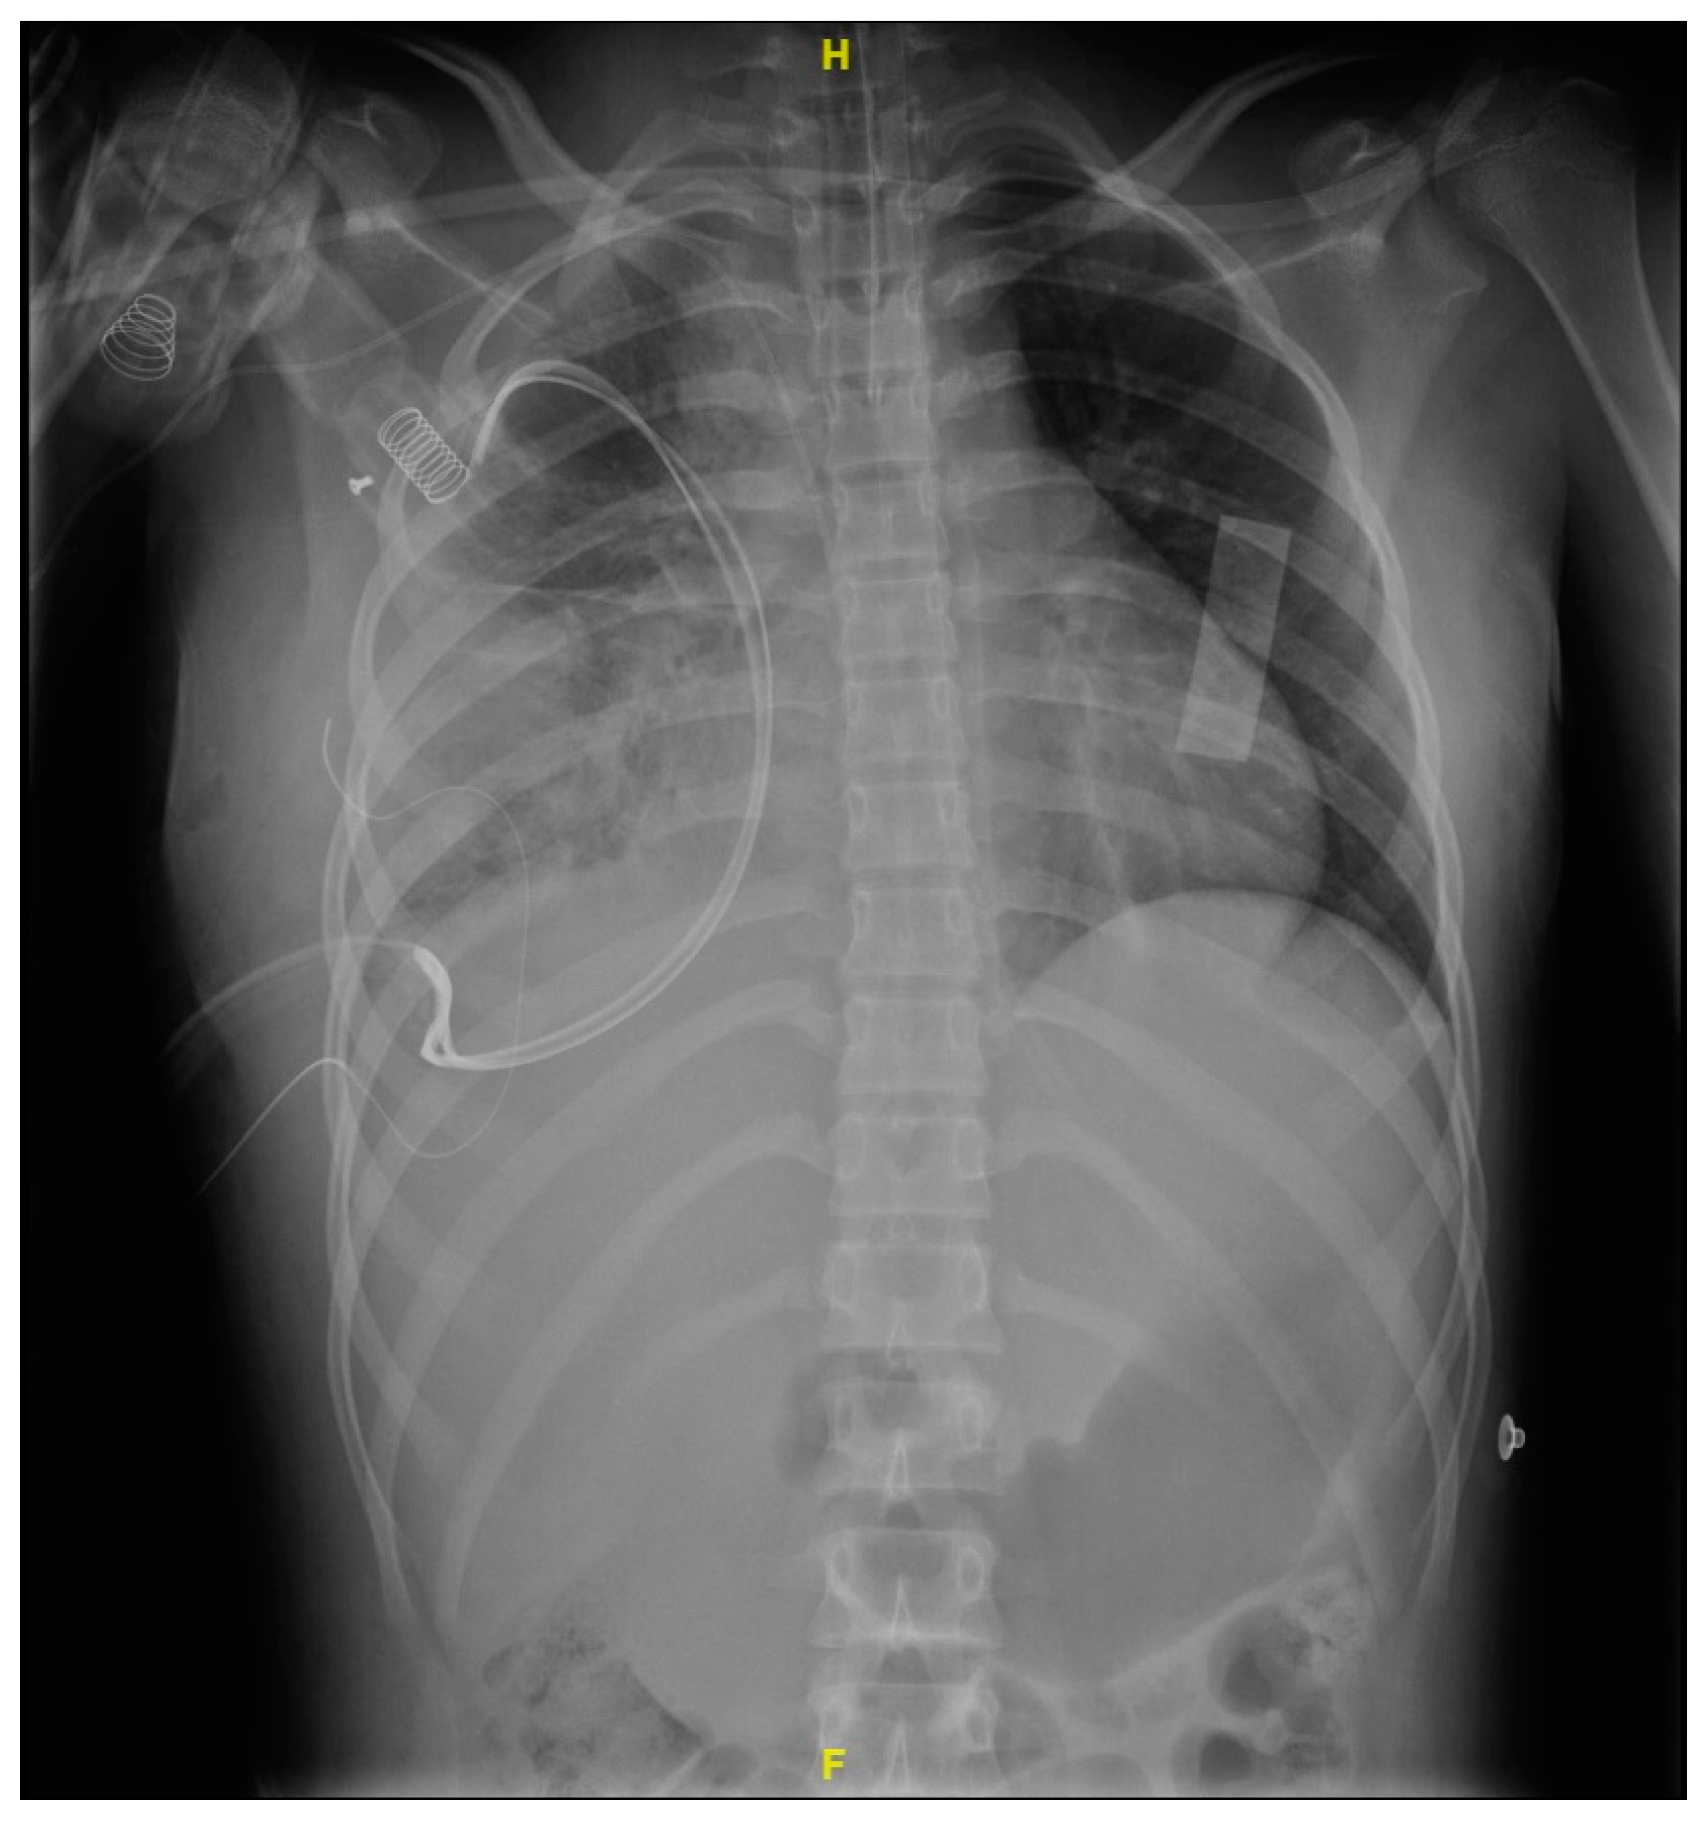

VAC therapy dressings were changed every 96 h. After four replacements, rehabilitation, and nutrition management, the patient was successfully discharged home with outpatient appointments, completing management with VAC therapy for 26 days with complete remission of the pulmonary and muscular infection process (Figure 6).

Figure 6. A chest X-ray taken after completely stopping the negative pressure therapy showed resolution of the infectious process, observing only persistent linear atelectasis.